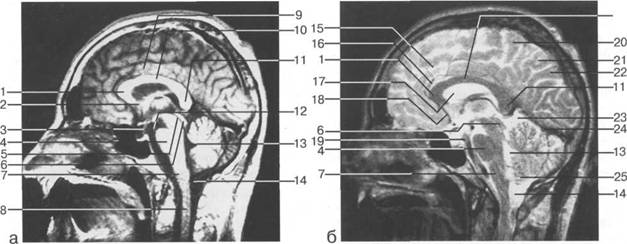

Задняя череп 13513u2010n 85;ая ямка представляет собой часть основания череп 13513u2010n 72;, ограниченную централь

Следует отметить, что в настоящее время оптимальным методом исследования структур задней череп 13513u2010n 85;ой ямки является МРТ, которая, в отличие от КТ, лишена артефактов от кост

Следует остановиться на анатомии подпаутинных пространств задней череп 13513u2010n 85;ой ямки IV 20 мм. Между основанием череп 13513u2010n 72; и нижней поверхностью мозга от большого затылочного отверстия вдоль ската и спинки турецкого седла простирается задняя базальная цистерна. В зави IV

цистерна четверохолмия; 14 -прямой синус; 15 -лобный рог; 16 - головка хвостатого ядра; 17 -перед

III ди зрительного бугра идет ретроталамическая цистерна, ориентированная во фронтальной

теменно-затылочная борозда; 11 - семиовальные